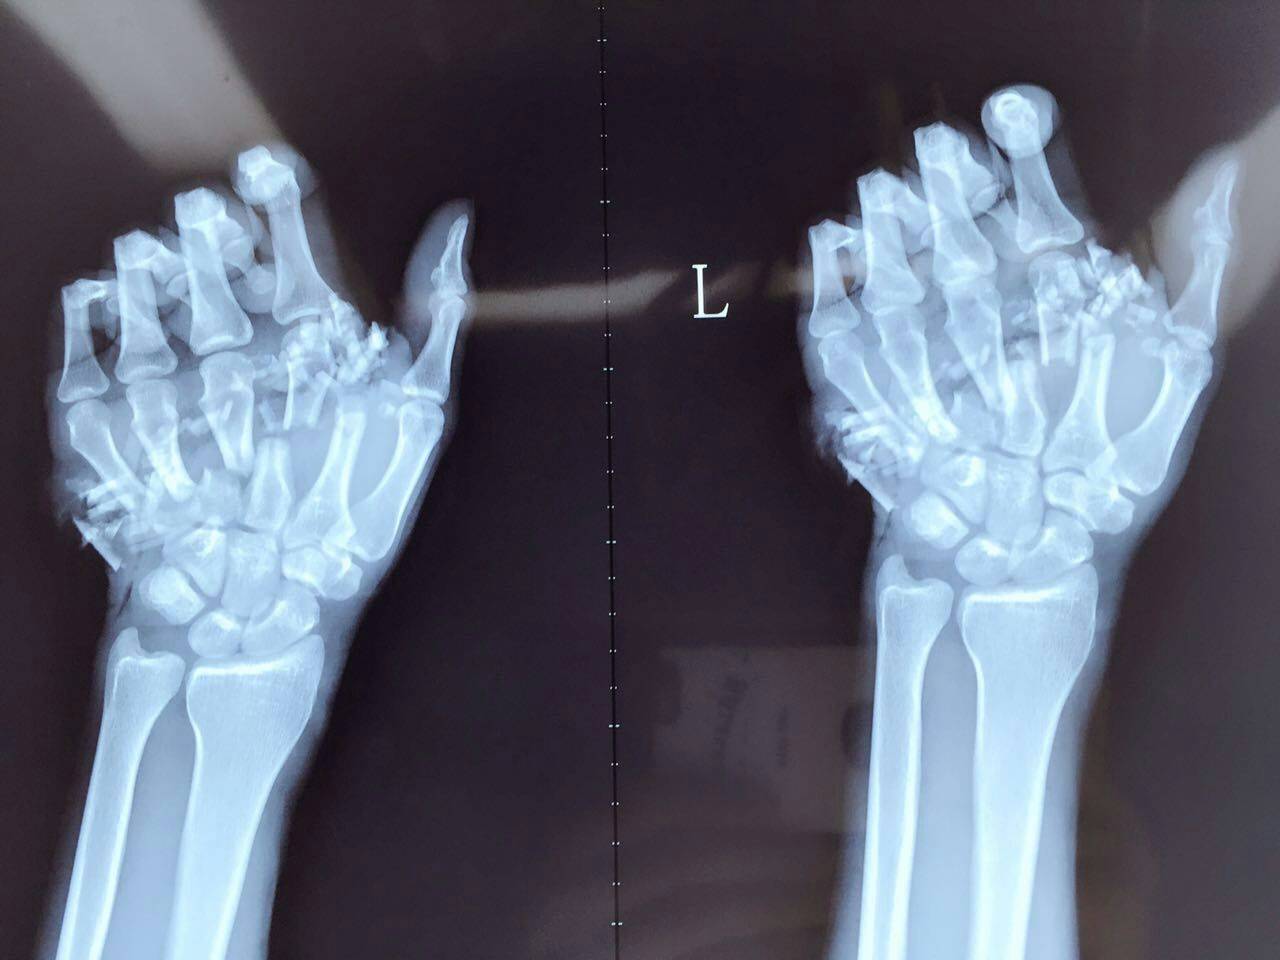

入院后醫(yī)生查體發(fā)現(xiàn)患者左手掌中間可見長約18厘米環(huán)形傷口,創(chuàng)面凹凸不平,污染嚴(yán)重,流血不止,骨折斷面及肌腱已經(jīng)嚴(yán)重外露出來,而且局部可以見到大量血凝塊附著。左第2-5指顏色蒼白,無血運(yùn),屬于手指離斷傷。

親們看到?jīng)]有,手掌內(nèi)骨頭都斷了,這真的是幾乎斷掌了